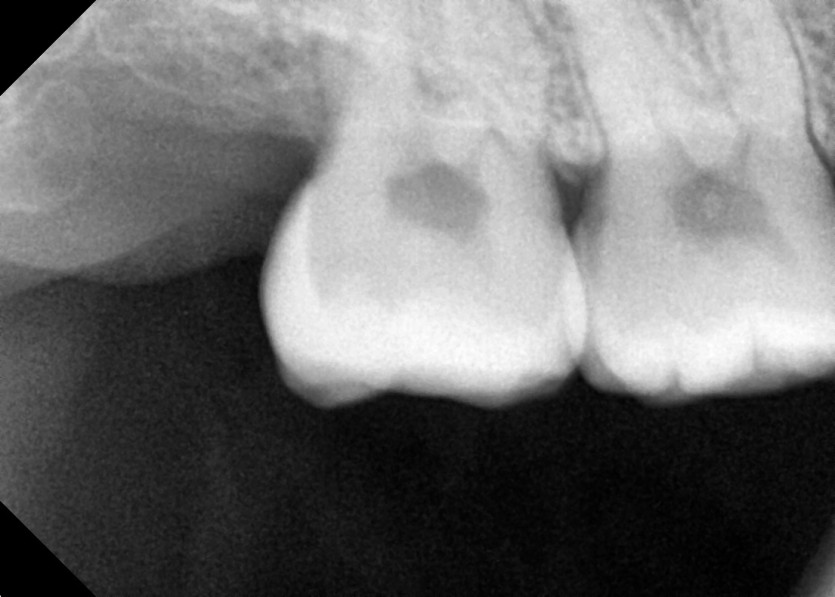

#18 사랑니 발치

구강 외과 전문의가 당일 발치했습니다.